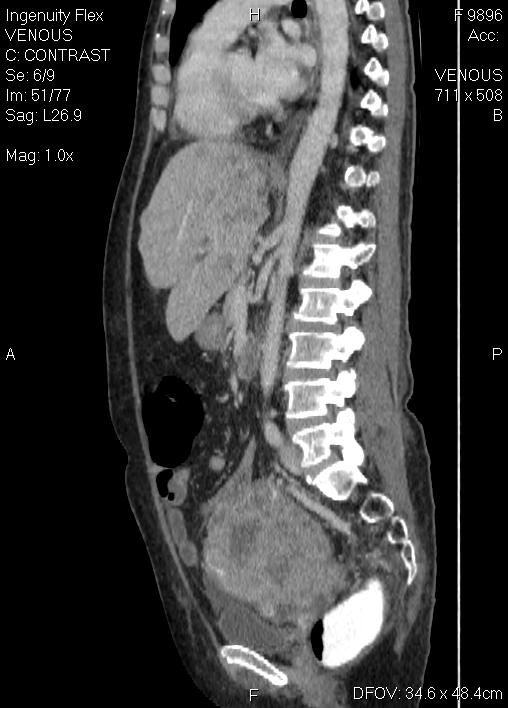

CT-ung thư cổ tử cung

CT-ung thư cổ tử cung 2

CT-ung thư cổ tử cung - di căn gan - tràn dịch màng phổi, ổ bụng

CT-ung thư nội mạc tử cung